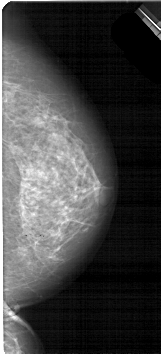

A_1885_1.LEFT_MLO

LEFT_MLO LINES 5491 PIXELS_PER_LINE 2971 BITS_PER_PIXEL 12 RESOLUTION 43.5 OVERLAY